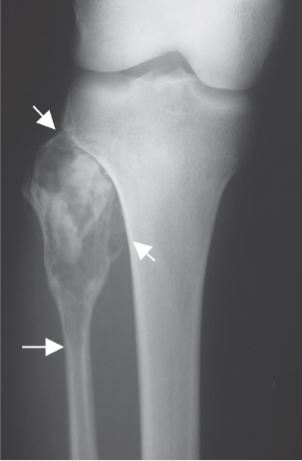

The compartment of the knee involves the tibia, fibula, patella, and distal femur bones. The fibula is a relatively small bone in comparison to the tibia (shin bone) and is a rare anatomic location for both primary and metastatic bone tumors. When a lesion does arise in this area, it typically occurs in the proximal fibula (part of bone closest to knee), followed by the diaphysis (middle part of bone), and finally the distal fibula (lower part of bone near ankle). The most common tumors to arise from the fibula, include chondrosarcoma, osteosarcoma, and benign aggressive cysts. Limb-sparing surgery can be performed for approximately 95% of tumors arising from the fibula. In some instances the extremity cannot be saved and an above the knee amputation is performed.